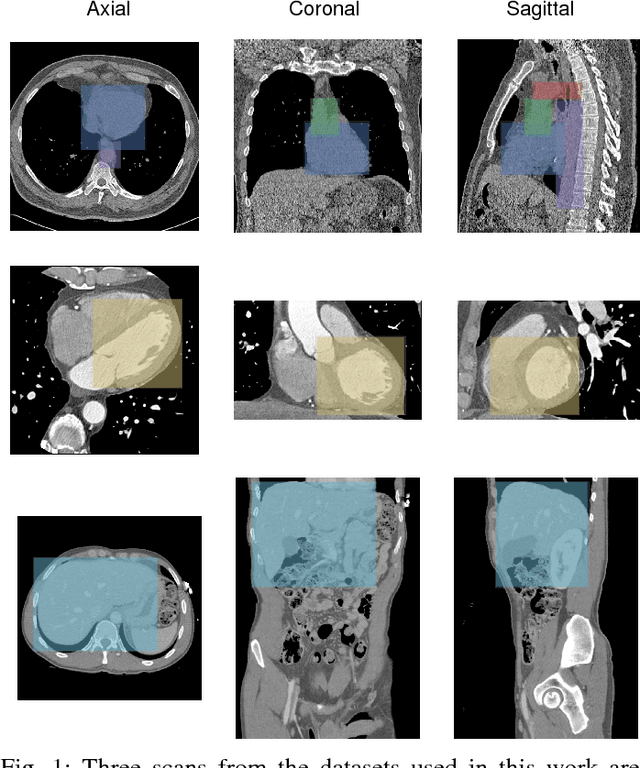

Abstract:Localization of anatomical structures is a prerequisite for many tasks in medical image analysis. We propose a method for automatic localization of one or more anatomical structures in 3D medical images through detection of their presence in 2D image slices using a convolutional neural network (ConvNet). A single ConvNet is trained to detect presence of the anatomical structure of interest in axial, coronal, and sagittal slices extracted from a 3D image. To allow the ConvNet to analyze slices of different sizes, spatial pyramid pooling is applied. After detection, 3D bounding boxes are created by combining the output of the ConvNet in all slices. In the experiments 200 chest CT, 100 cardiac CT angiography (CTA), and 100 abdomen CT scans were used. The heart, ascending aorta, aortic arch, and descending aorta were localized in chest CT scans, the left cardiac ventricle in cardiac CTA scans, and the liver in abdomen CT scans. Localization was evaluated using the distances between automatically and manually defined reference bounding box centroids and walls. The best results were achieved in localization of structures with clearly defined boundaries (e.g. aortic arch) and the worst when the structure boundary was not clearly visible (e.g. liver). The method was more robust and accurate in localization multiple structures.